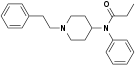

Anilidopiperidines